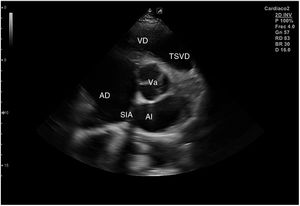

Para obtener los planos apicales la sonda se coloca sobre el latido cardiaco en el ápex, bajo la mamilla izquierda, a la altura del quinto espacio intercostal, con la marca dirigida a la izquierda del paciente y angulado en dirección al hombro derecho. Este plano, apical de 4 cámaras (fig. 8), muestra las 4 cavidades cardiacas y las válvulas auriculoventriculares vistas desde el ápex (fig. 9). En él, el plano del anillo tricuspídeo se sitúa más cerca del ápex que el mitral y el VD se ve más trabeculado. Es la vista de elección para medir la superficie de la AI, comparar el tamaño de ambos ventrículos y descartar la presencia de disfunción y/o dilatación ventricular. Angulando el transductor hacia anterior se obtiene el plano apical de 5 cámaras, que permite observar el tracto de salida del VI y valorar el flujo a través de la válvula aórtica (fig. 10); y al rotarlo 90° en sentido antihorario, el apical de 2 cámaras, que muestra las paredes anterior e inferior del VI (fig. 11).

Para obtener el plano subcostal, con el paciente en decúbito supino, se orienta la sonda desde el epigastrio hacia el hombro izquierdo, con una inclinación de unos 15°, utilizando el hígado como ventana acústica. Esta es una ventana muy útil en pacientes con enfermedad pulmonar. En este corte (fig. 12) aparecen las 4 cámaras separadas por sus correspondientes septos; el VD es el más próximo al transductor, por lo que aparece en la parte más superior y próxima en la pantalla.